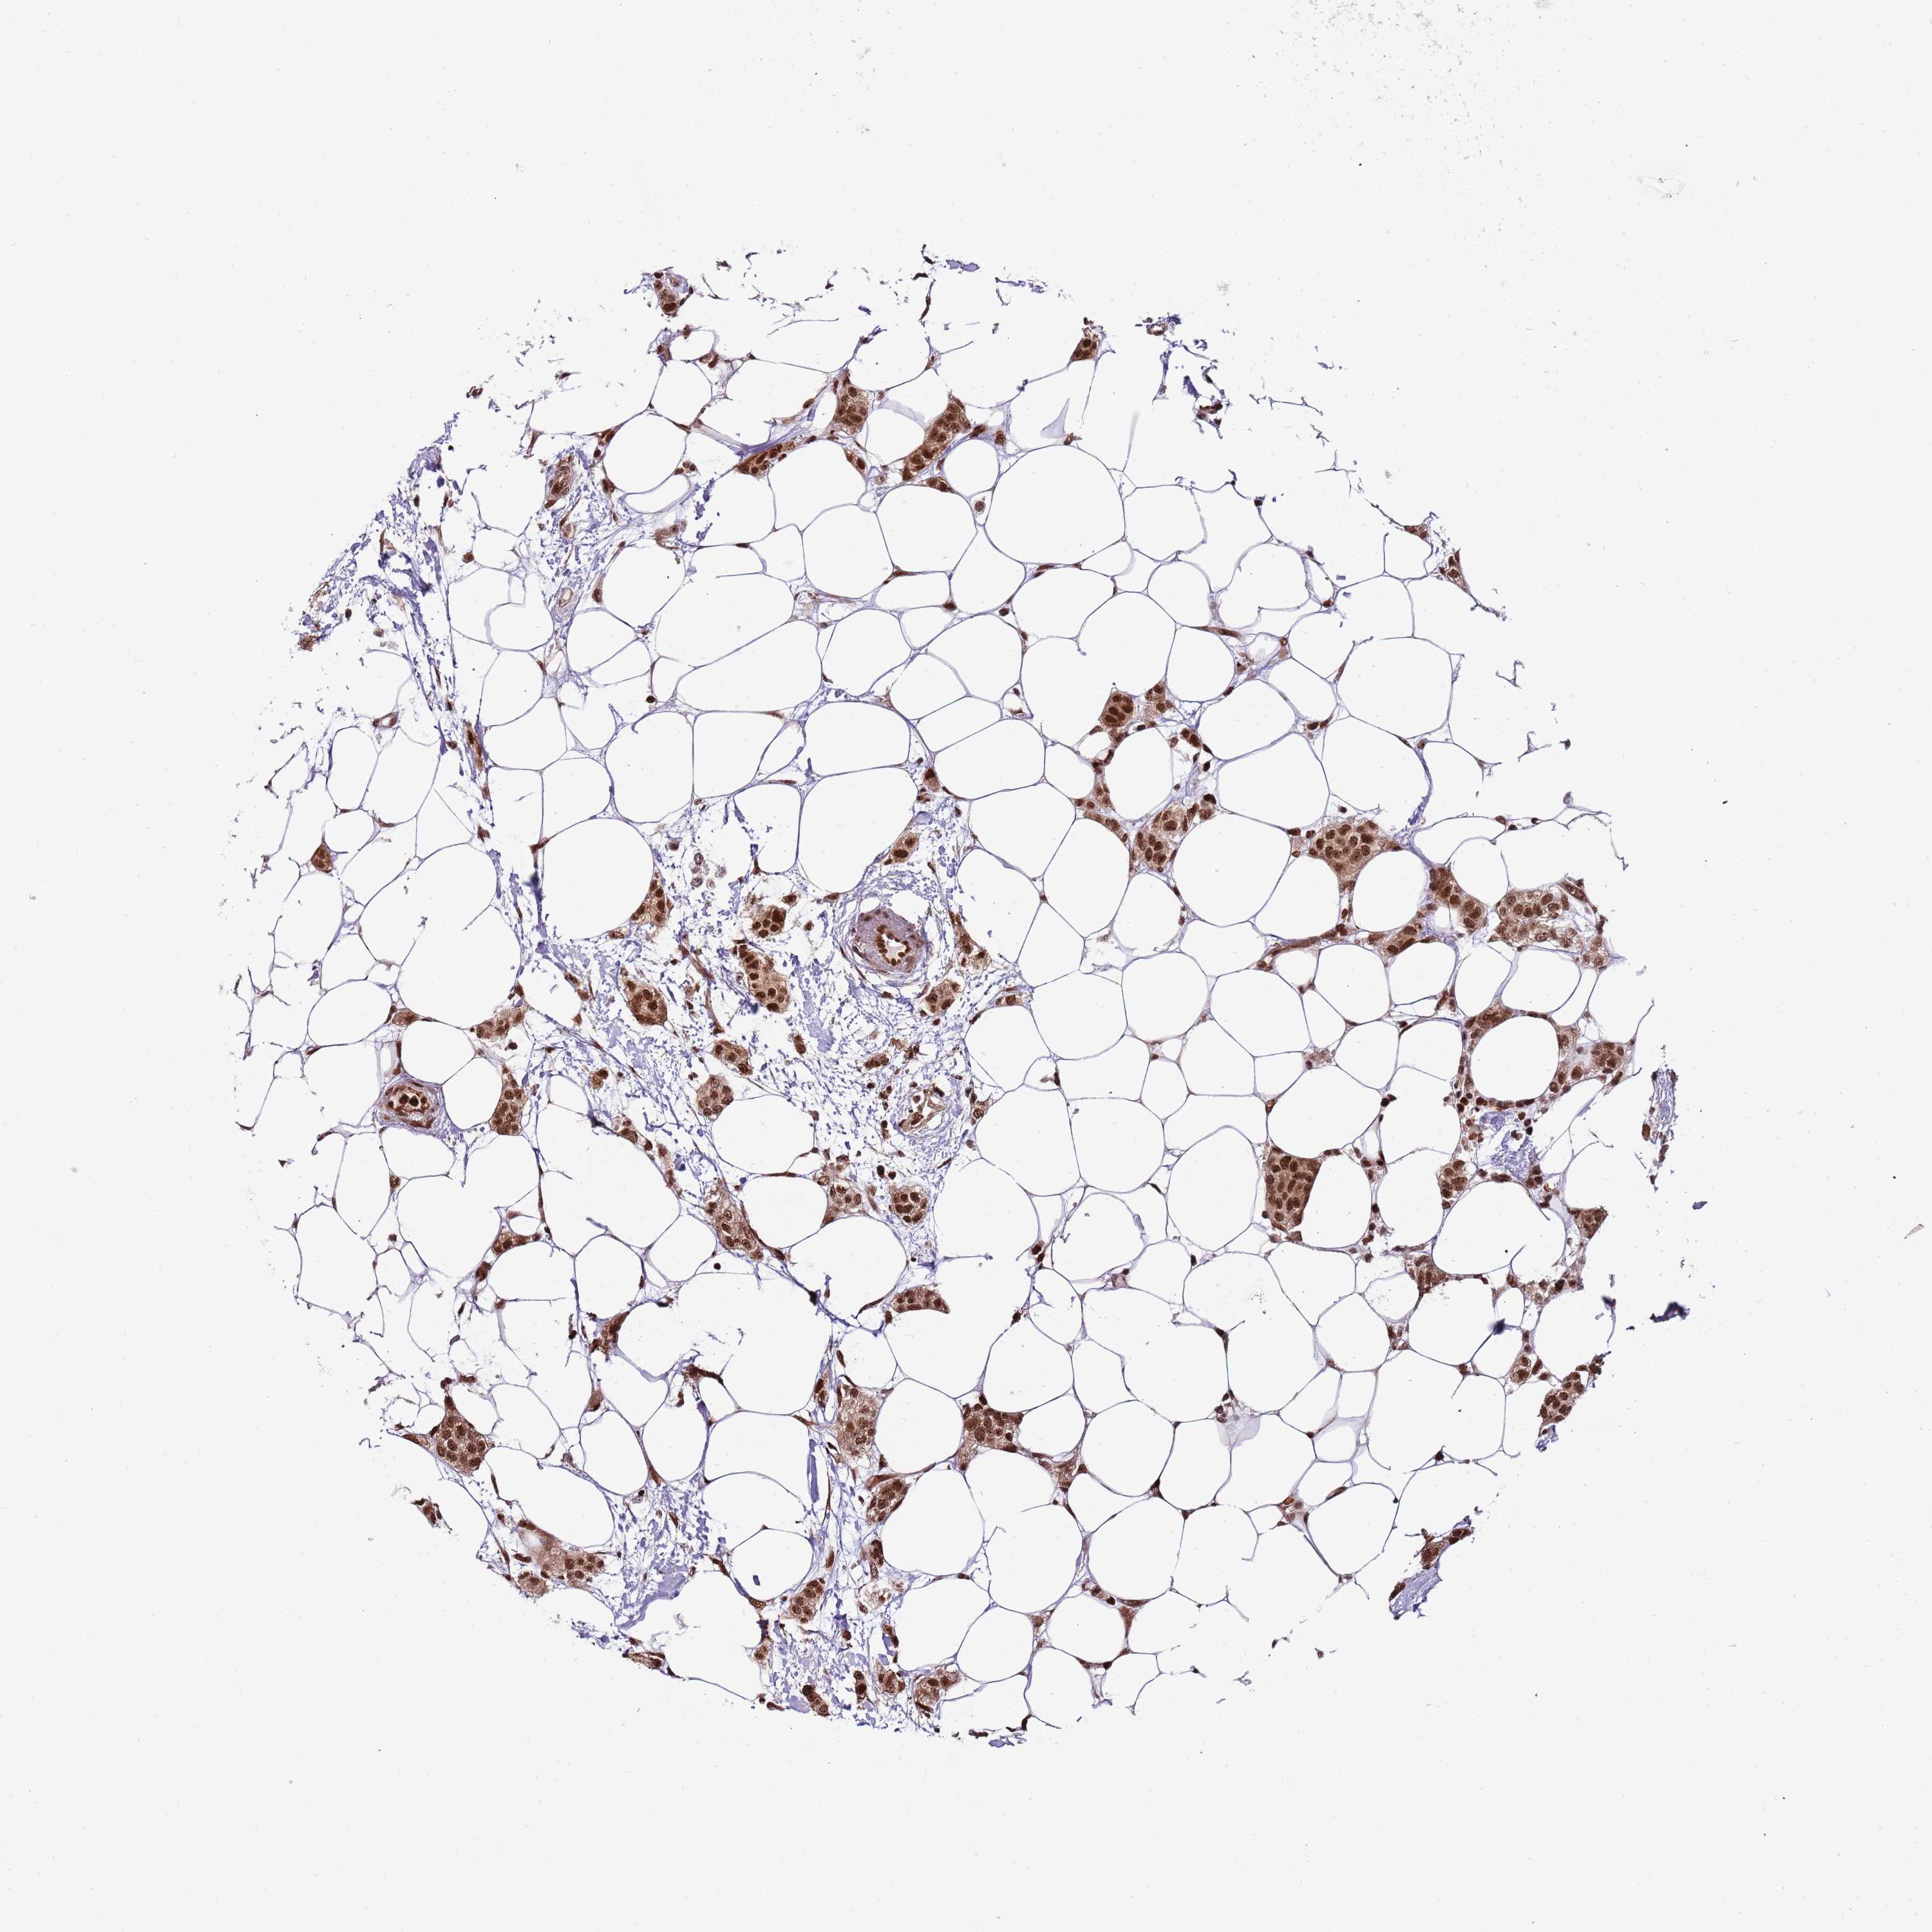

CANCER BREAST CANCER Show tissue menu

BRCA TCGA BRCA VALIDATION PROTEIN EXPRESSION